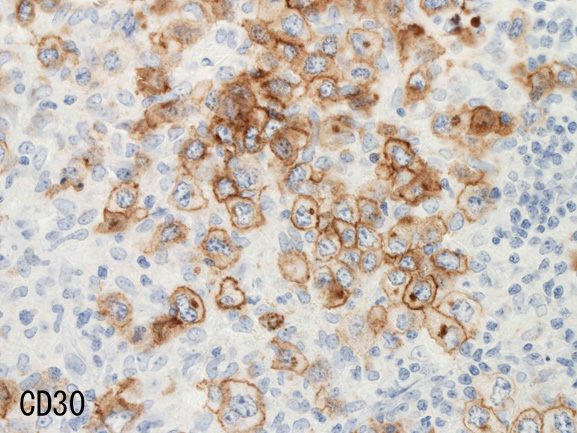

腫瘍細胞はCD20+, CD30+, CD15-, PAX-5+, Oct.2+, BOB.1+(Oct2, BOB1は田丸先生の染色結果), EBER-ISH+, EBNA2-

| CD20 | PAX-5 | CD30 | EBER-ISH+ |